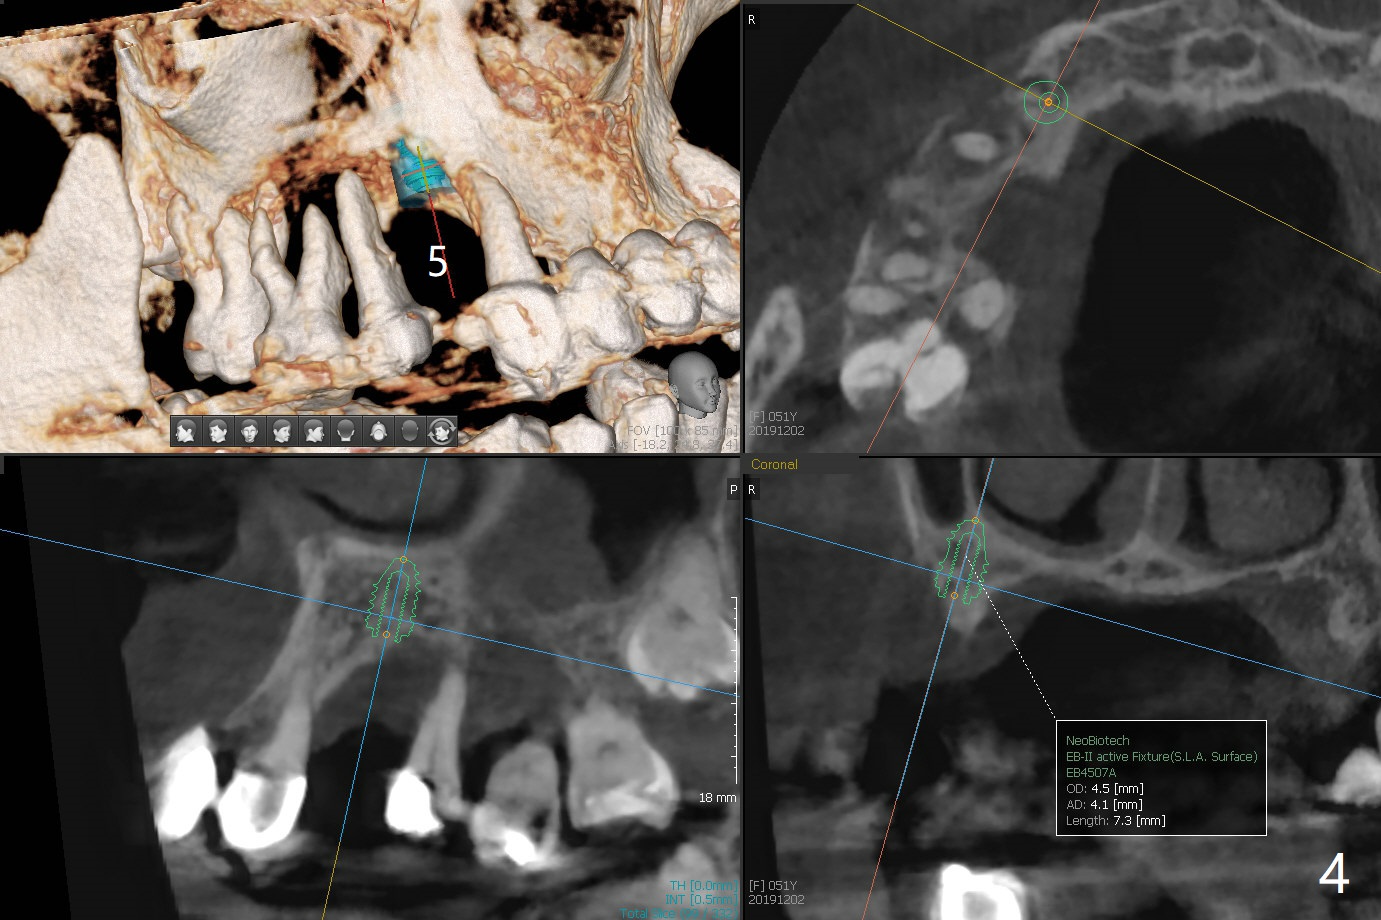

A 51-year-old woman has poor dentition with chronic periodontitis (Fig.1). She has financial constraint, but refuses RPD, insisting upon UR posterior implants first. After discussion of severe bone loss, she agrees with bone graft first (Fig.2-4). Since the bone atrophy is the most severe at #3 (Fig.5 coronal section; L: lingual), sinus lift (Fig.6 arrow) is conducted after extraction (black). Use sticky bone (Fig.7 red circles) and Titanium-reinforced Cytoplast (white) for socket preservation. Or if Magicore is able to achieve primary stability (Fig.8 green), an abutment (pink) will be placed for an immediate provisional (white). The latter are capable of holding bone graft in place. Since bone loss at #2 and 4 is less severe (Fig.9 sagittal section), their roots will act as walls to keep bone graft (Fig.11) in place after #3 extraction (Fig.10).